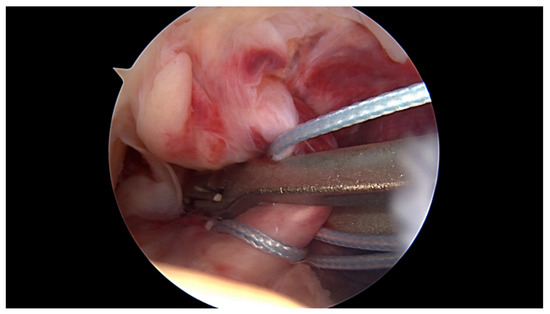

Primary Proximal ACL Repair: A Biomechanical Evaluation of Different Arthroscopic Suture Configurations

by Steffen B. Rosslenbroich, Andrea Achtnich, Cathrin Brodkorb, Clemens Kösters, Carolin Kreis, Sebastian Metzlaff, Benedikt Schliemann and Wolf Petersen

J. Clin. Med. 2023, 12(6), 2340; https://doi.org/10.3390/jcm12062340 - 17 Mar 2023

Purpose: Several suture techniques have been described in the past for direct ACL repair with poor healing capacity and a high re-rupture rate. Therefore, we investigated a refixation technique for acute primary proximal ACL repair. The purpose of this study is to [...] Read more.

Purpose: Several suture techniques have been described in the past for direct ACL repair with poor healing capacity and a high re-rupture rate. Therefore, we investigated a refixation technique for acute primary proximal ACL repair. The purpose of this study is to compare the biomechanical properties of different suture configurations using a knotless anchor. Methods: In this study, 35 fresh-frozen porcine knees underwent proximal ACL refixation. First, in 10 porcine femora, the biomechanical properties of the knotless anchor, without the ligament attached, were tested. Then, three different suture configurations were evaluated to reattach the remaining ACL. Using a material testing machine, the structural properties were evaluated for cyclic loading followed by loading to failure. Results: The ultimate failure load of the knotless anchor was 198, 76 N ± 23, 4 N significantly higher than all of the tested ACL suture configurations. Comparing the different configurations, the modified Kessler–Bunnell suture showed significant superior ultimate failure load, with 81, 2 N ± 15, 6 N compared to the twofold and single sutures (50, 5 N ± 14 N and 37, 5 ± 3, 8 N). In cyclic loading, there was no significant difference noted for the different configurations in terms of stiffness and elongation. Conclusions: The results of this in vitro study show that when performing ACL suture using a knotless anchor, a modified Kessler–Bunnell suture provides superior biomechanical properties than a single and a twofold suture. Within this construct, no failure at the bone–anchor interface was seen. Clinical relevance: Since primary suture repair techniques of ACL tears have been abandoned because of inconsistent results, ACL reconstruction remains the gold standard of treating ACL tears. However, with the latest improvements in surgical techniques, instrumentation, hardware and imaging, primary ACL suture repair might be a treatment option for a select group of patients. By establishing an arthroscopic technique in which proximal ACL avulsion can be reattached, the original ACL can be preserved by using a knotless anchor and a threefold suture configuration. Nevertheless, this technique provides an inferior ultimate failure load compared to graft techniques, so a careful rehabilitation program must be followed if using this technique in vivo. Full article

Show Figures

Figure 1